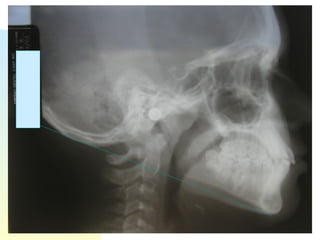

Tracings/Analyses Count the number of asterisks Represents standard deviations from the accepted norm of that particular analysis McNamara, Ricketts, Steiner

What does all that gobbledy-gook mean? 1. Where’s the maxilla is in relation to cranium? 2. Where’s mandible in relation to cranium? 3. Where’s mandible in relation to maxilla? 4. What direction is patient likely to grow? 5. Where is upper incisor in relation to maxilla? 6. Where is lower incisor in relation to mandible? 7. What is inter-incisal angle? Helps determine how much the problems are skeletal vs dental discrepancies...

Other factors: airway, level of compliance, facial symmetry

Tracings/Analyses Count thenumber of asterisks Represents standard deviations from the accepted norm of that particular analysis McNamara, Ricketts, Steiner

What does allthat gobbledy-gook mean? 1. Where’s the maxilla is in relation to cranium? 2. Where’s mandible in relation to cranium? 3. Where’s mandible in relation to maxilla? 4. What direction is patient likely to grow? 5. Where is upper incisor in relation to maxilla? 6. Where is lower incisor in relation to mandible? 7. What is inter-incisal angle? Helps determine how much the problems are skeletal vs dental discrepancies...

Other factors: airway,level of compliance, facial symmetry